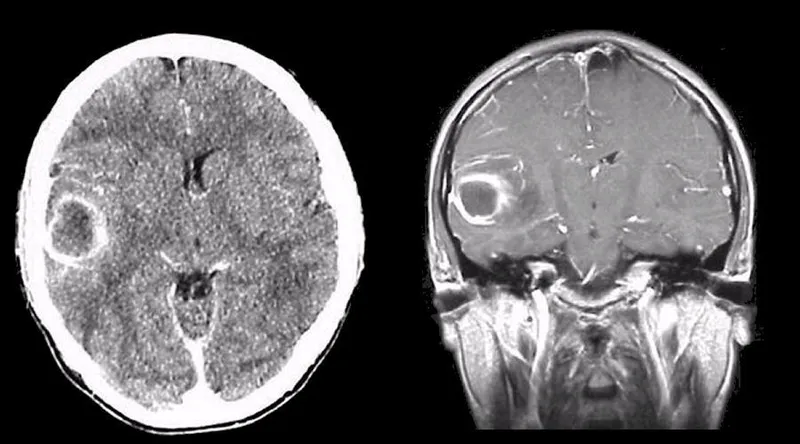

- Imaging: Ring-enhancing lesion (CT/MRI).

⭐ Triad of brain abscess (fever, headache, focal neurological deficit) is seen in <50% cases.